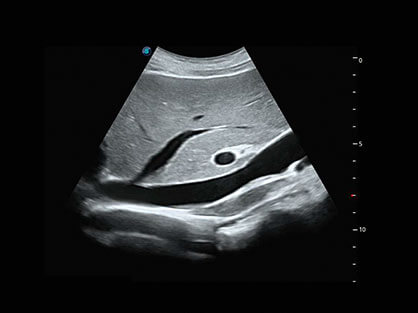

微米成像技术提升了对组织斑点噪声信号的抑制能力,并进一步强化边界信息,从而获得清晰图像。

0.5mm厚度的薄层切片显像,可清晰显示微小病灶的连续断面。